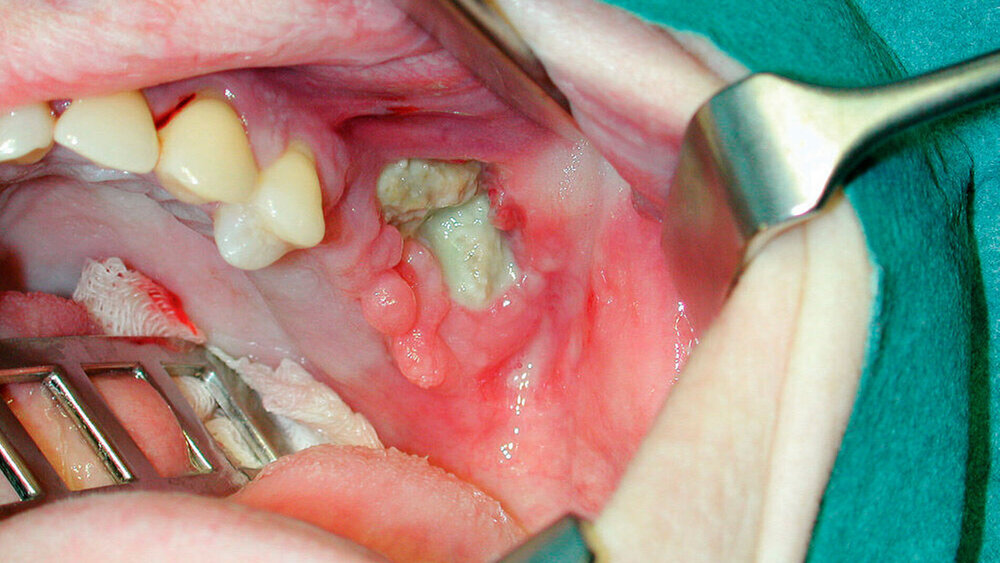

Es erfolgte eine Zahnextraktion, obwohl die Patientin über einen Zeitraum von 15 Monaten aufgrund ihrer Osteoporose Bisphosphonate (jede Woche 70 mg) genommen hatte. Vor der Extraktion wurde nicht nach der Einnahme von Bisphosphonaten gefragt.

Die Extraktionswunde heilte trotz der Bisphosphonat-Therapie langsam, aber vollständig aus. Bei einem weiteren Zahn erfolgte später sicherheitshalber keine Extraktion, vielmehr wurde der Wurzelrest endodontisch behandelt und mit einer Kompositkappe auf Gingivaniveau dauerhaft versorgt.